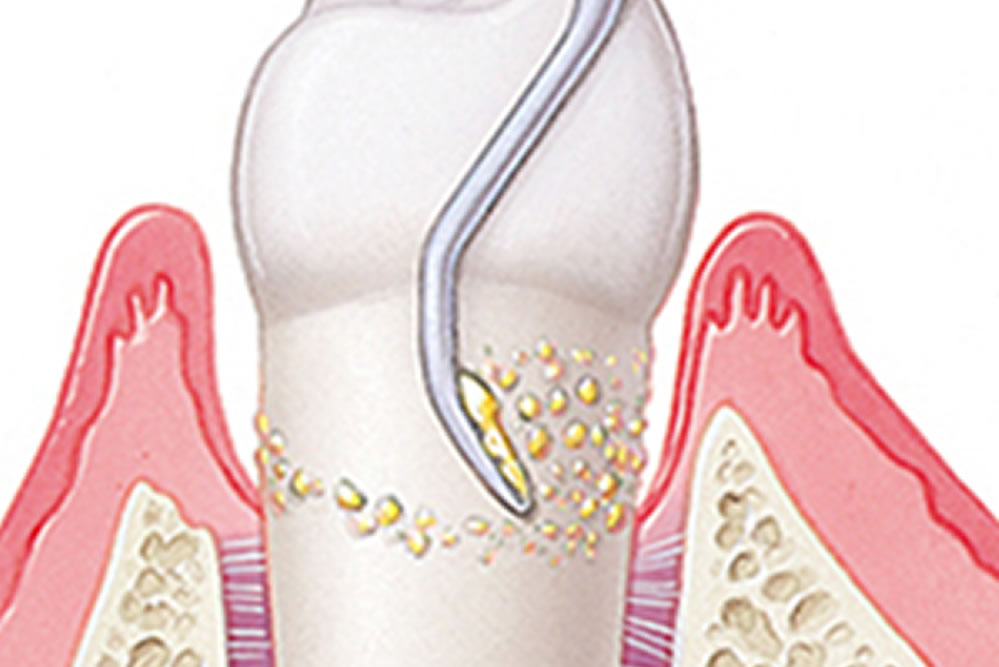

マイクロスコープで歯周ポケット5mm以上の歯石を除去している動画

この動画は実際にBiVi歯科・矯正歯科にて、歯周ポケット5mm以上の歯石を除去している様子です。肉眼、もしくは数倍の拡大鏡ではとてもではありませんが、見えません。一般歯科では歯周外科か抜歯のどちらかを宣告されるケースと思いますが、こちらの患者さまは歯周病が改善し、抜歯や外科処置は一切行わずに済みました。

歯周病治療における最大の敵である細菌は、主に固まりとなって歯石という形で認識できるようになります。この歯石が歯と歯ぐきの間(歯周ポケット)に挟まって炎症を起こし、歯肉や歯槽骨を溶かすのが歯周病です。

歯周病治療における最大の敵である細菌は、主に固まりとなって歯石という形で認識できるようになります。この歯石が歯と歯ぐきの間(歯周ポケット)に挟まって炎症を起こし、歯肉や歯槽骨を溶かすのが歯周病です。

歯周ポケットの奥深く7~8mmまで付着した歯石はもはや肉眼では把握できず、除去することはおろか、気づくことすらできません。

しかし、肉眼の20倍以上に視野を拡大することができるマイクロスコープを使用することによって、精密かつ低侵襲な歯周病治療が実現します。

3mmまでの浅い歯周ポケットでも処置後に14%歯石の取り残しがあり、4~6mmでは24%、6mm以上では50%取り残しているというエビデンス(医学的根拠)が発表されています。

ルートプレーニングとは、特殊な器具で歯周ポケットの奥にこびりついた歯石や汚れを除去する方法です。

ルートプレーニングとは、特殊な器具で歯周ポケットの奥にこびりついた歯石や汚れを除去する方法です。

中度歯周病の場合、ある程度の深さにまで歯石が食い込んでいきますので、器具を入れ込む関係上、治療時には出血が伴い痛みも想定されます。